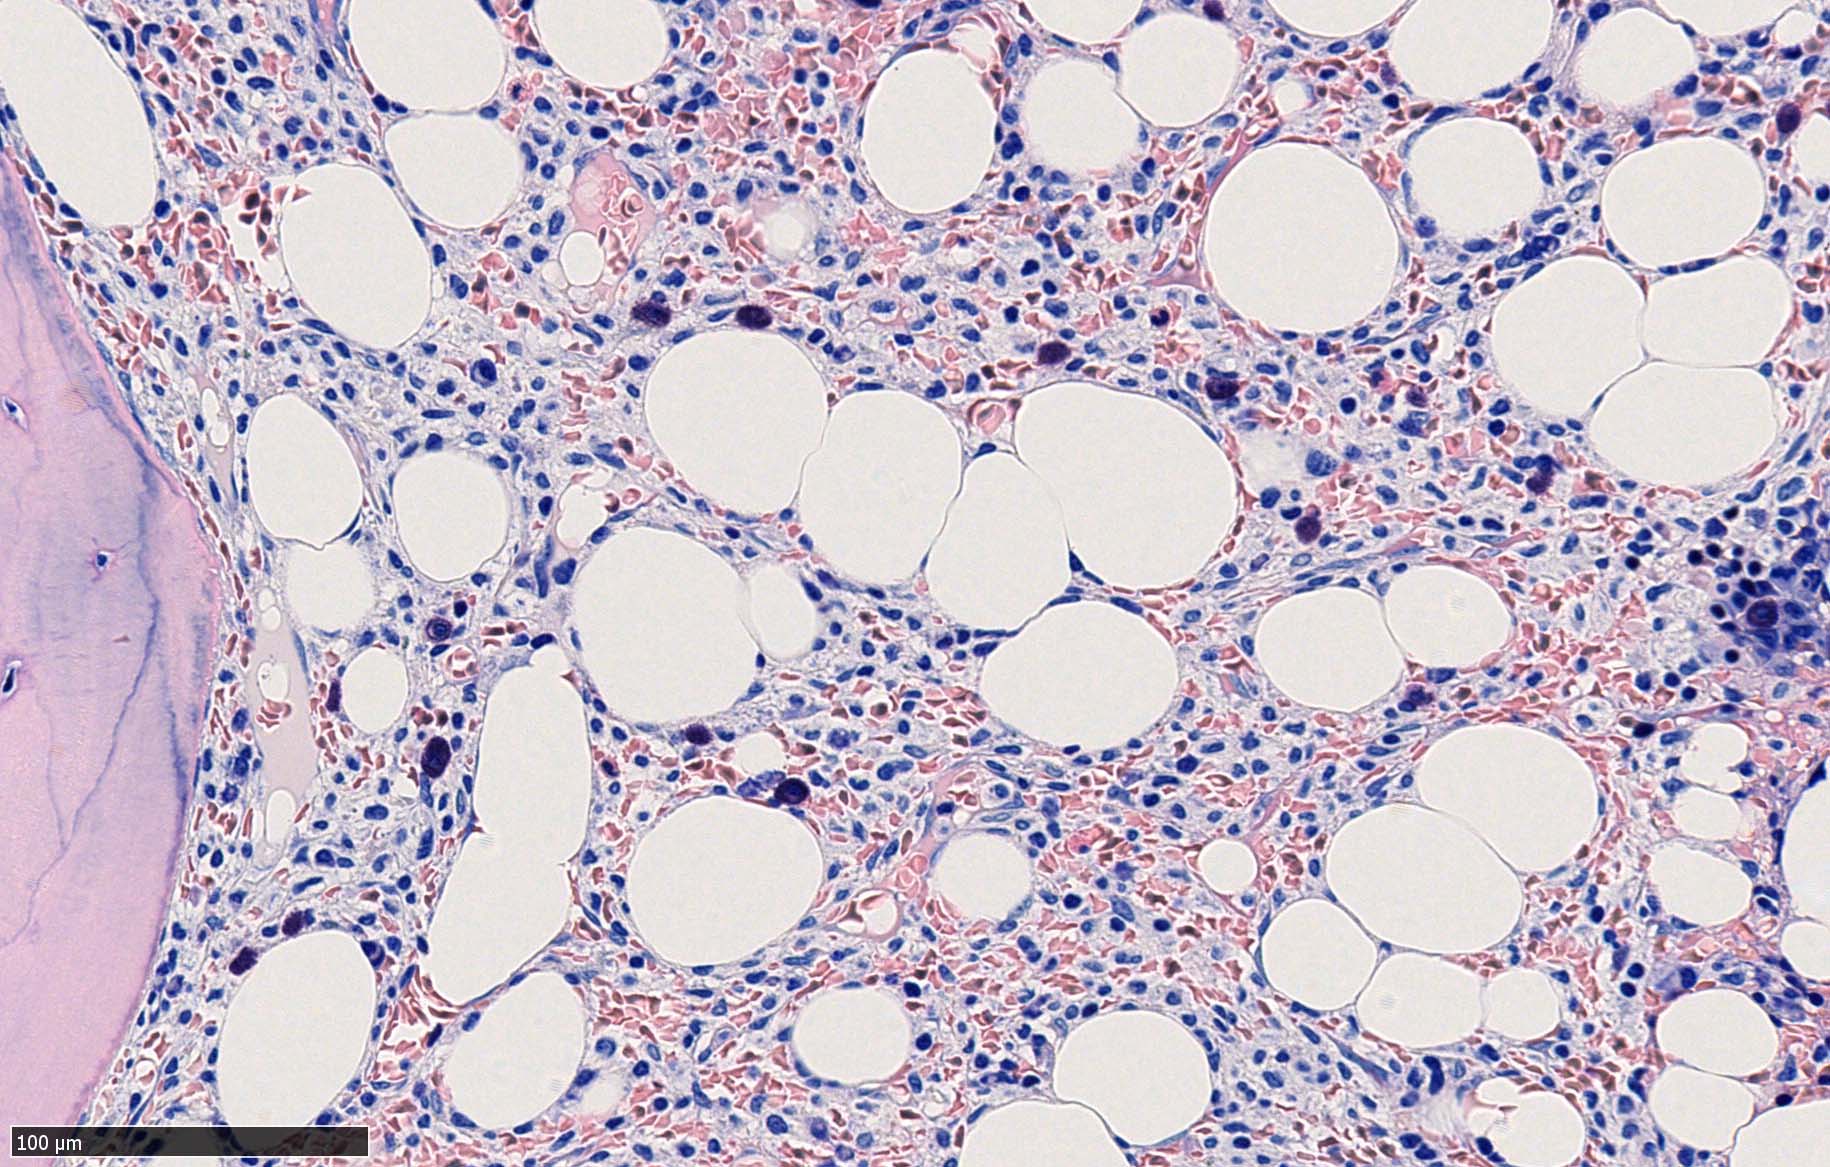

骨髄生検

bone marrow trephine biopsy: dry tapのため骨髄生検が行われる. cellularityは40-80%とhypercellular marrow. 流れのある細胞配列は線維化を疑わせる.

ASD-G 低倍率所見では赤芽球血島は幼若赤芽球の集簇巣が散在する, 顆粒球系細胞(ASDに赤く染色される)は減少,granulopoietic hypoplasiaを呈する.疎な集簇を示すmast cellsの増加がある.

ASD-G陰性の細胞がびまん性に増加しているように見える.

ASD-Giemsa陰性の細胞がシート状に増殖する. 核はクロマチン濃染, 核小体は不明瞭.類円形, 卵円形, くびれを持つ多稜形核, 長円形いびつで屈曲した核, など多彩. 細胞質は淡清色調, 広く淡明. 赤芽球血島は幼若赤芽球のみで形成される異形成像を示す. やや離れて成熟赤芽球が疎な集簇を示す.

Ag染色では, 疎な弾性線維が増生し,増殖細胞を小胞巣状に分画するいわゆる「lymphomatoid pattern」を呈する. 本例では, Mgkに異形成所見がある.